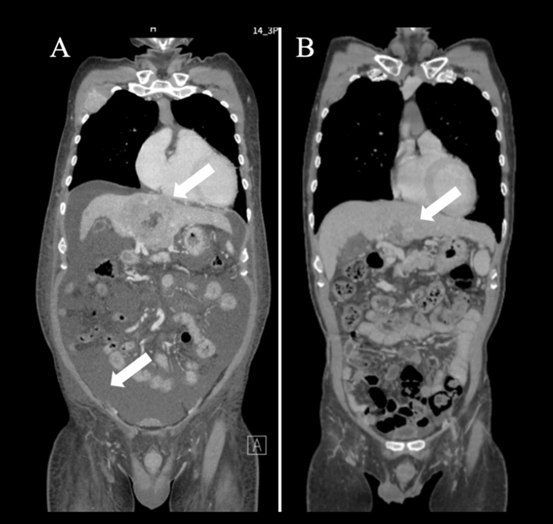

2024年8月《Cureus》的另一篇报告记录了61岁晚期肝细胞癌患者的治疗经历。

该患者接受DC疫苗+NK细胞+纳武利尤单抗的联合方案后,病情显著改善:肝脏储备功能恢复,肿瘤体积大幅缩小,腹水减少。

原本卧床不起的他,3个疗程后可下床活动;7个疗程后肝功能达标,从 “只能姑息治疗” 转为可接受标准治疗,彻底摆脱了 “无药可救” 的困境。